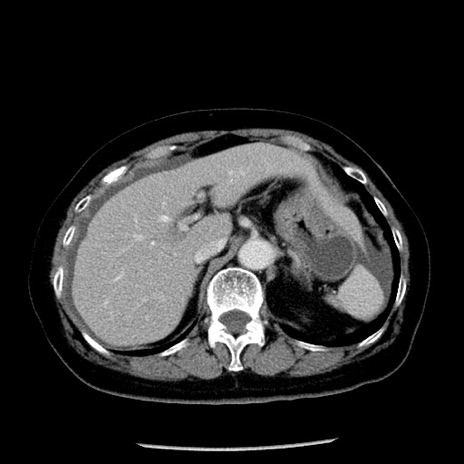

冠状断像